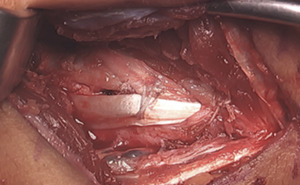

On either side of the concavity of the sublime tubercle, 2 converging 3.5 mm drill holes are made. These tunnels are transitioned with a curved curette and a doubled vicryl suture is passed with a curved needle.

A 2.7 mm drill hole is made at the apex of the sublime tubercle 4 to 5 mm distal to the joint line but proximal to the ulnar tunnels. A 3.5 mm swivel lock anchor loaded with collagen coated fiber tape is placed in the tapped drill hole.

At the base of the medial epicondyle, with caretaken to lateralize the proximal tunnel, a 2.5 mm drill bit is used to make a starter hole for the larger drill bit to follow.

This initial hole is then over drilled with either a 4.0- or 4.5-mm drill bit to a depth of 15 to 17 mm.

A 2.5 mm drill bit is is used to create two divergent tunnels through the proximal cortex of the medial epicondyle. Utilizing a Hewson suture passer, doubled over 2-0 vicryl sutures are passed.